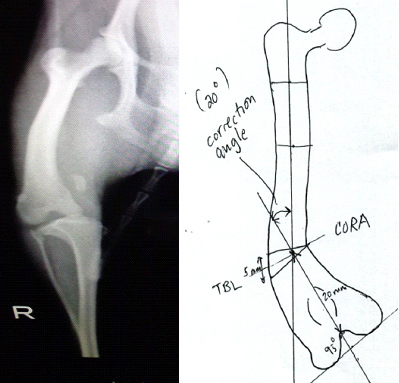

最後に上記の犬の膝蓋骨内側の脱臼(グレードⅣ)の手術計画の行程表の1例を示します。(Dr. Brian Beale.の指導による行程表)

- 内側の関節包の解離(支帯解放術)

- 滑車形成術

- 大腿骨脛骨の矯正骨切り術

- 膝蓋骨の溝を評価して、脛骨粗面転位術 又は、脛骨の矯正骨切り術又は、何もしない

- 膝蓋骨支持縫合又は外側支帯

- 関節包の外側筋膜の縫縮術